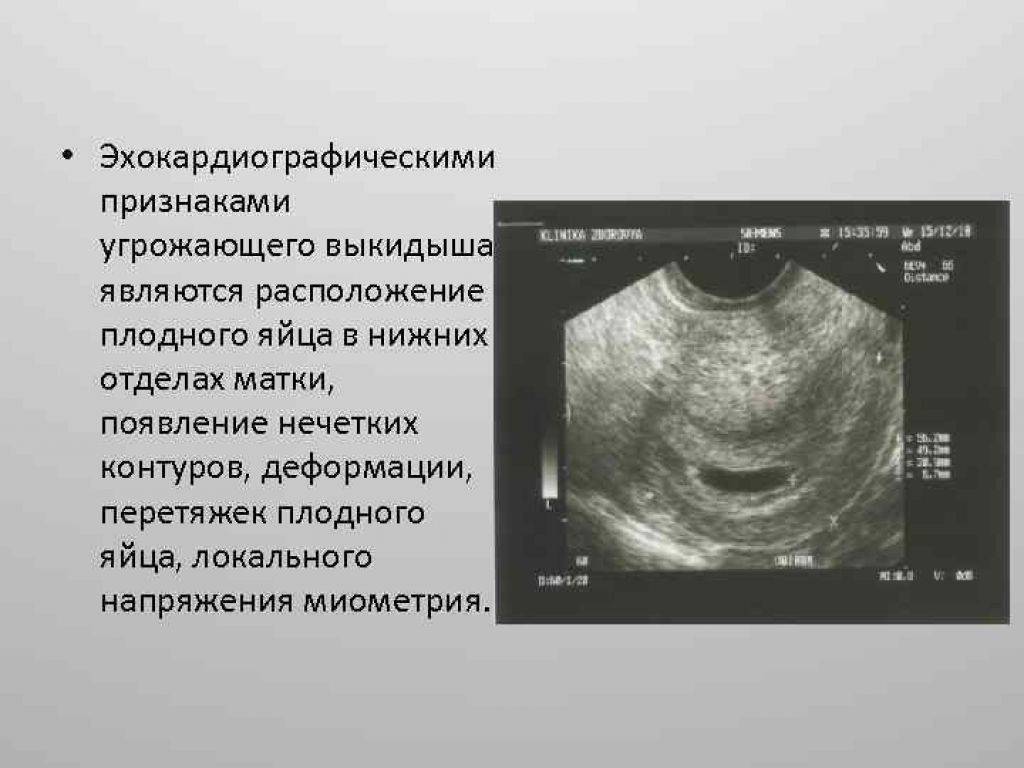

- из-за небольшой отслойки плаценты или повышенного тонуса матки возможно деформирование яйца. Если начать лечение сразу, имеется большой шанс нормального исхода беременности;

- неправильное прикрепление плодного яйца. Если оно прикрепится в самом низу матки, то угроза выкидыша велика, необходим полный покой женщине, иногда возможен постельный режим до самых родов;